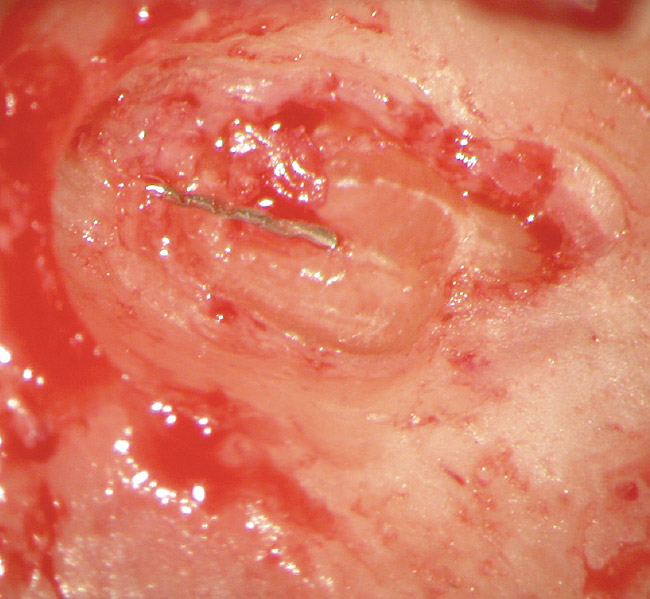

Figure 4a  Tooth No. 30 Nonsurgical root canal treatment had been completed 5 years before. The periapical radiograph revealed periradicular radiolucencies (periapical and in the furcation area).

Figure 4a

Figure 4b  The patient was asymptomatic, and periodontal probing depths were within normal limits; however, a new crown restoration was planned. Nonsurgical endodontic re-treatment was initiated. The intracoronal picture shows the previously treated 4 canals with infected gutta-percha filling.

Figure 4b

Figure 4c  Under high magnification, a furcation canal (Figure 4C) and a third distal canal (Figure 4D) were located.

Figure 4c